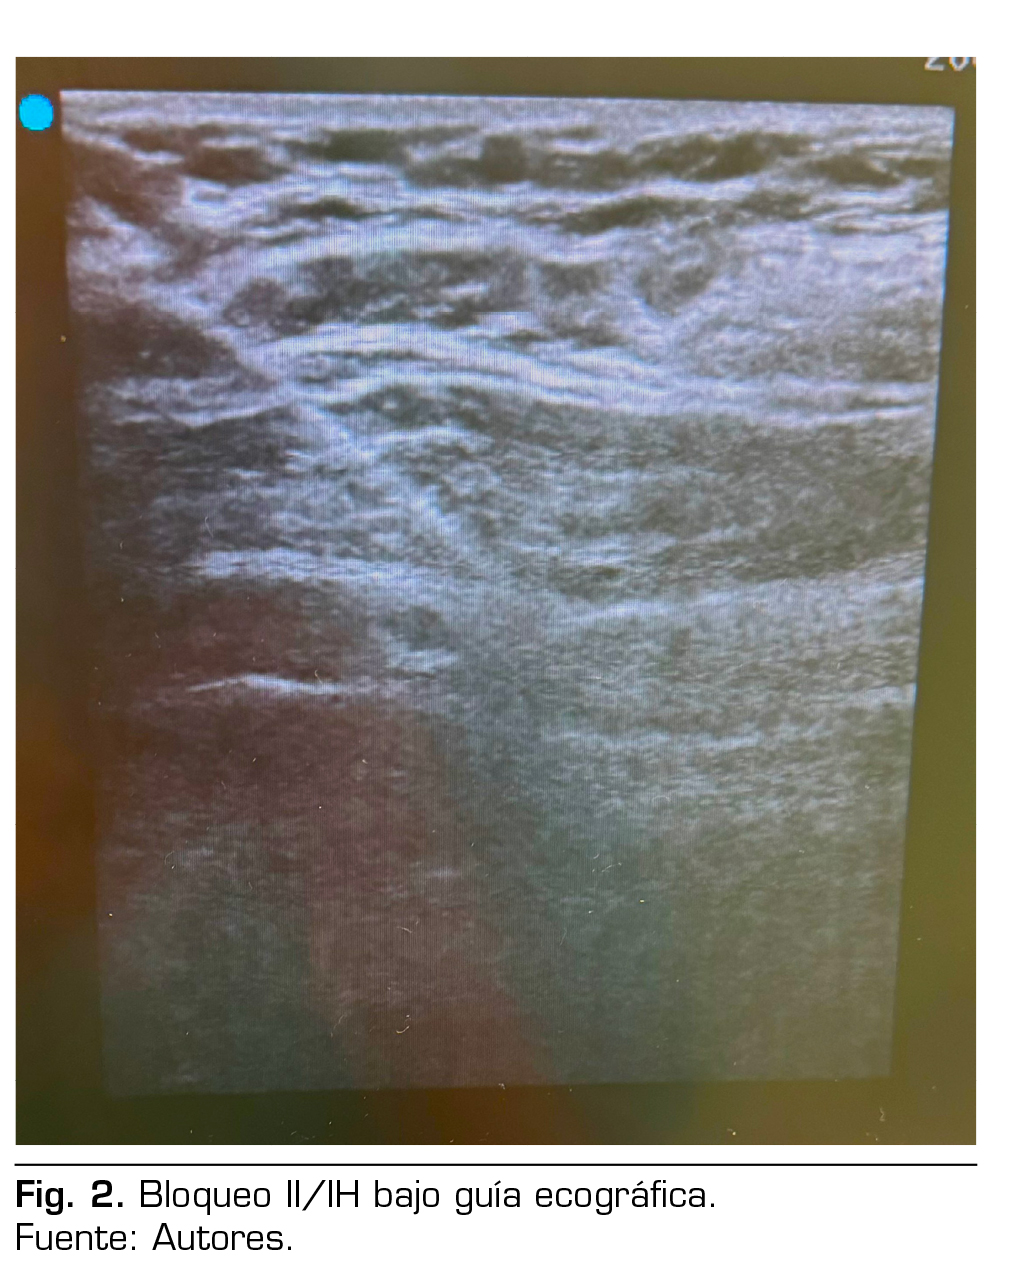

Presentación de caso: Presentamos el caso clínico de un paciente adulto mayor de 88 años ASA III, sometido a una hernioplastia inguinal electiva, bajo anestesia regional: bloqueo II/IH bajo guía ecográfica más sedación, manejo analgésico complementario con paracetamol y antinflamatorios, alta de cirugía médica ambulatoria a su domicilio y control postoperatorio sin complicaciones.

Case presentation: We present the clinical case of an 88-year-old adult patient ASA III, for elective inguinal hernioplasty, under regional anesthesia: Ilioinguinal-Iliohypogastric block under ultrasound guidance plus sedation, complementary analgesic management with paracetamol and anti-inflammatory drugs, discharge from outpatient surgery to his home and postoperative control without complications.

Figura 2